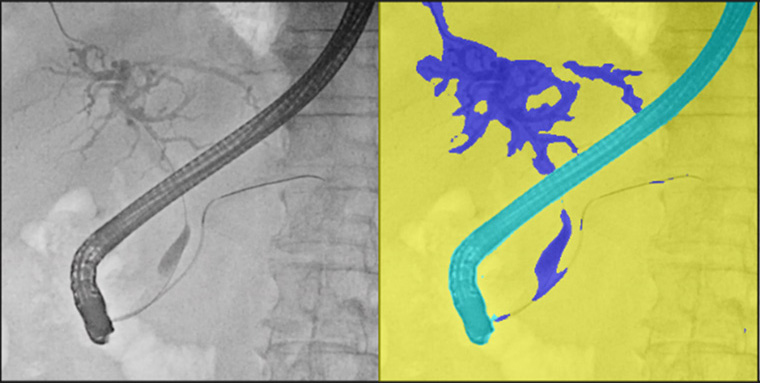

また、今回発売する二つのモデルは、2025年4月に発売したソフトウェア「VisualAID-ERCPプランニング-」*7にも対応。本ソフトウェアは、ERCP中にCUREVISTAシリーズで撮影したX線透視画像上に3Dで作成した胆管・膵管の画像を重ねて表示することで、臓器との重なりなど解剖学的構造の把握が容易になることが期待できる。本ソフトウェアでは、これまでCT画像とMRCP画像*8で3D画像を作成する必要があったが、今回新たにCT画像のみで3D画像を作成できるようになった。これにより、MRI撮影を実施しない医療機関での対象被検者の増加が見込まれる。さらに3D画像作成時にCT画像とMRCP画像の位置合わせの作業が不要となることでワークフローの向上が期待できる。同社のIT技術とX線透視装置を連携させた新しいワークフローにより、医師の診療の高度化・効率化に貢献する。

(2)造影剤の使用量低減に貢献する画像処理機能「Boost C*13」

AI技術を活用して開発された造影剤強調処理により、ERCP実施時に造影された胆管領域を検出し、コントラストを強調する。本機能を使用しない透視画像よりも、胆管領域の視認性が向上する。本機能により、1検査あたりの造影剤使用量を低減し、被検者の身体的負担の軽減が期待できる。